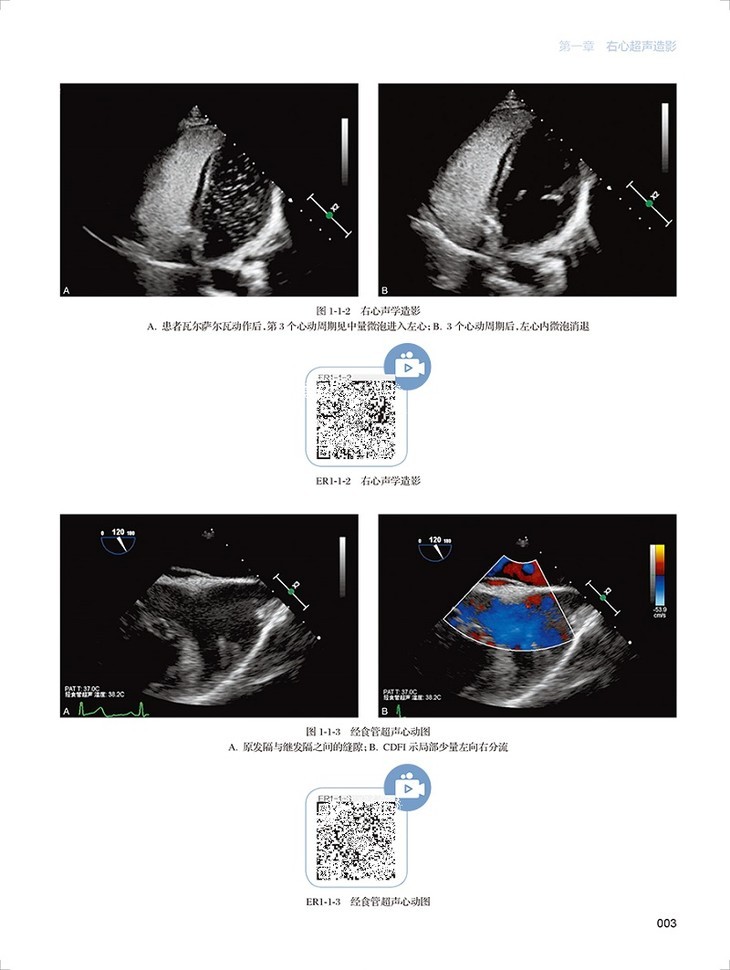

心血管超声造影图鉴共有文字内容60千字,图片454幅,视频212个。全书分为三章三十一节内容,分为左心超声造影、右心超声造影和血管造影三个板块,包括了卵圆孔未闭右向左分流、肺动静脉瘘、永存左上腔静脉、房间隔缺损封堵术后评估右向左的残余分流、部分型肺静脉异位引流、应激性心肌病、左心房黏液瘤、心腔内血栓等疾病的超声造影表现。每个病例分为病史概要、常规超声图像、超声造影图像、经食道超声心动图和超声造影要点五个小标题,内容精炼、脉络清晰、一目了然。各个病例配了多张彩图和视频进行对照,读者可以扫描图片右侧二维码观看视频,方便快捷。